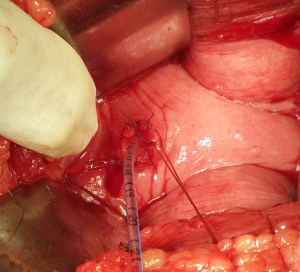

An impacted stone in a ureterocele, removed through open cystostomy and meatotomy.

A difficult lap chole, thick-walled gallbladder adherent to live bed which bled furiously, controlled with packing.